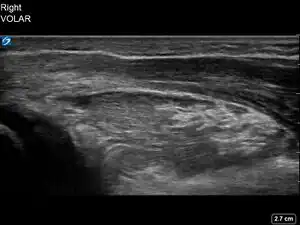

| 2 | Buckle (Torus) Fracture | "Bent" | ![]() | ||